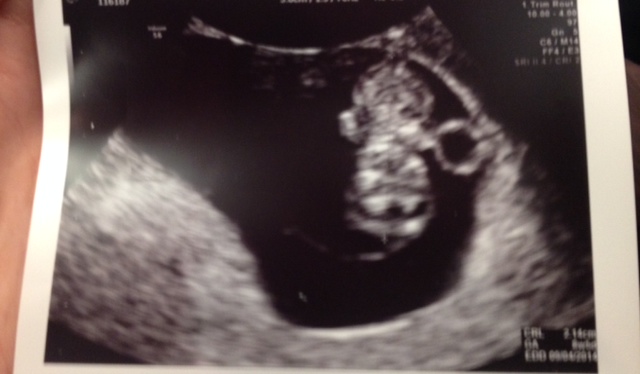

DH and I went to our first appointment and ultrasound this morning. The doctor said that everything looks great and that our baby is measuring right on date (8w5d). We got to see/hear the heartbeat and we're just so excited about it all! DH was so cute taking pictures of the monitor screen - I explained to him that we would get pictures. Lol.

Here is one of the photos that we got. The baby is upside down in this - head at the bottom, yolk sac on the right side, little limbs off to each side.